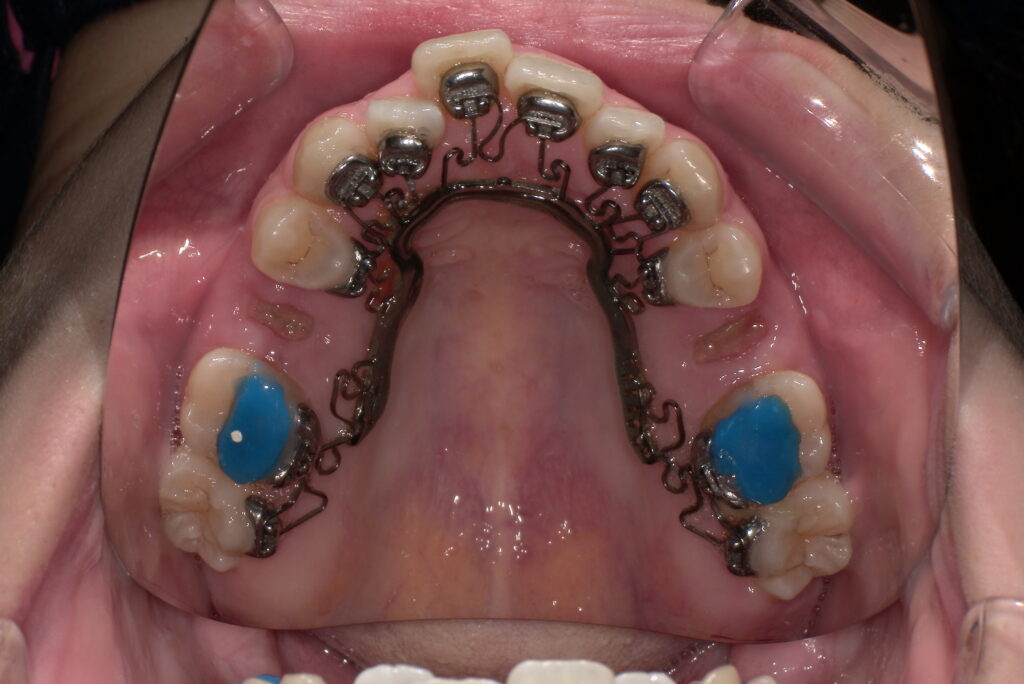

上顎

(青い材料は下の歯が上の装置にぶつからないよう、咬み合わせを一時的に上げる材料です)

下顎